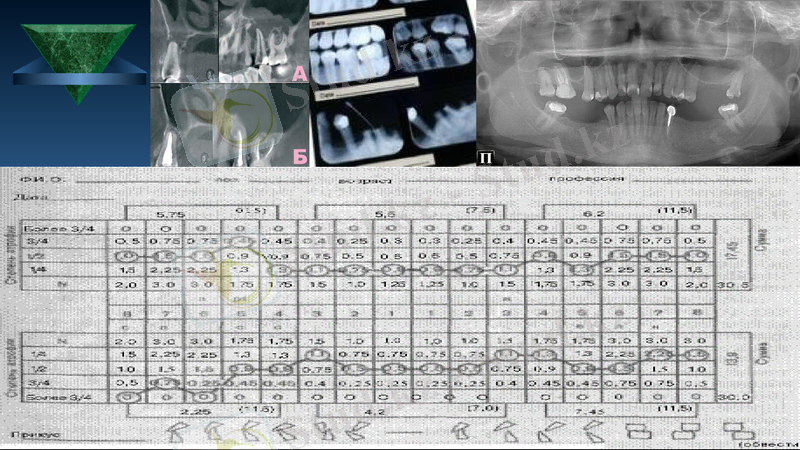

Рентгенологиялық зерттеу ( панорамды, ауызішілік, ауызсыртылық, тістем кезіндегі, контрастты заттар қолдану арқылы)

Диагностикалық мүсіндерді зерттеу

Бұл әдісті жүргізу үшін ең алдымен қалып аламыз. Қалыптан ғаныштан мүсін құямыз. Кейін арнайы артикуляторға орнатамыз. Ең алдымен анықтайтынымыз:

Тіс доғасының формасы, деформациялары

Таңдайлық және тілдік төмпешіктердің қатынасы

Жоғарғы жақ тістерінің төменгі жақ тістерін жабуы

Окллюзиялық қисықтың сипаттамасы

Тіс қатары окклюзиялық бетінің деформациясы

Тіс сауытының қисаю осі

Рентгенологиялық зерттеу әдісі

Ең кең тараған зерттеу әдісі болып табылады. Рентгенологиялық зерттеу әдісі арқылы біз тіс қуысының ерекшелігін, периодонтальды саңылау жағдайын, компактты табақшаның және альвеолярды өсіндінің жағдайын көре аламыз. Сонымен қатар рентгенограммада тіс түбірлерінің көлемін, бағытын, ретенирленген және комплектті тістерді анықтай аламыз. Қабатты рентген сурет арқылы төменгі жақтың структурасын, самай-төменгі жақ буынының жағдайын, патологиялық өзгерістердің бар-жоқтығын білеміз. Рентгенологиялық суреттердің кең тараған тәсілдері: панорамды сурет, ауызішілік рентген сурет, томография, телерентгенография

Одонтопародонтограмма - тістің сауыт бөлімінің және пародонттың функциональды жағдайын зерттеу нәтижесін кесте түрінде белгілеу. Бұл кестеде тіс формуласы және тістердің жағдайы көрсетіледі.

С - тіс жегі; Р - ұлпа қабынуы; Рт - периодонтит; R - түбір; П - пломба; К - сауыт; И - жасанды тіс

Пародонт жағдайы: N - патологиялық өзгеріс жоқ, 0 - тіс жоқ; ¼ - атрофияның бірінші дәрежесі; ½ - атрофияның екінші дәрежесі, ¾ - атрофияның үшінші дәрежесі